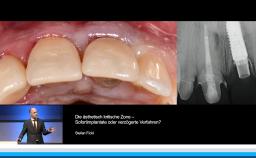

Herr Dr. Hentschel diskutiert in dieser Präsentation, die im Rahmen des deutschen ITI Kongresses in Dresden gehalten wurde, aus der Sicht eines Anwenders die Frage, ob kurze Implantate Augmentationen vermeiden können. Dabei stellt er retrospektive Daten aus der eigenen Praxis vor und legt den Fokus auf den seitlichen Unterkiefer.

Er definiert kurze Implantate als kleiner gleich 8 mm und vergleicht diese mit längeren Implantaten größer gleich 12 mm. Dabei geht er auch knapp auf prothetische Aspekte der Versorgung kurzer Implantate, sowie die Frage des Belastungszeitpunktes auf der Basis der ISQ Messung, ein. An klinischen Fällen zeigt er den Sinn des Einsatzes von Soft Tissue Level Implantaten in dieser Indikation auf.